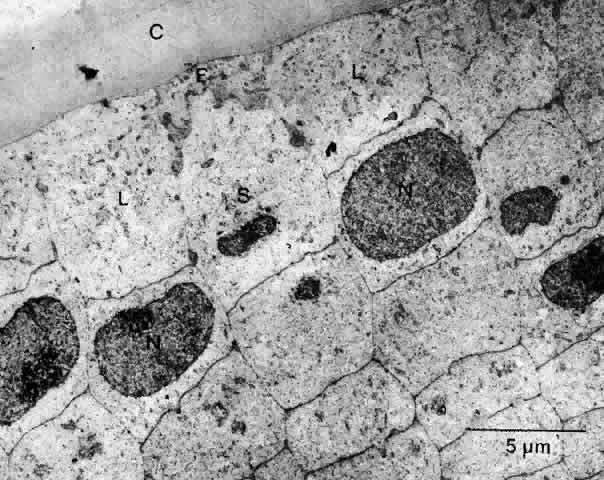

Unlike the cells of the central zone, the germinative zone cells, located peripherally on a whole-mount preparation, actively divide (see Fig. 15). In sagittal section (see Fig. 15), where they are located pre-equatorially, the cells are smaller and more cuboidal and contain more mitochondria than cells of the central zone.84 The cells are joined by a large number of lateral interdigitations (Fig. 16).

Fig. 16. A transmission electron micrograph of cells near the germinative zone of an adult human lens epithelium. The cells contain a number of organelles typical of epithelia. The lateral borders between the cells are highly convoluted and are marked by numerous desmosomes (arrows) and junctional complexes located near the apices. C, capsule; F, fiber; N, nucleus.